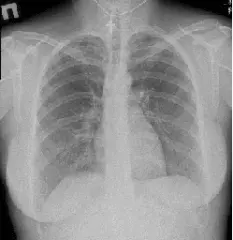

Рентген грудного відділу робитися в 2-ух проекціях (в прямій та боковій), в положенні лежачи. А, в разі викривлення, для оцінки різниці в відхиленні хребетного стовпа, робляться знімки в одній проекції, стоячи і так само лежачи – це дає можливість судити про стабільність або нестабільність хребта.

Для проведення рентгенографії в прямій проекції, рентгенолаборант укладає пацієнта на спину на процедурний стіл. Випромінювач рентген-апарату направляється на досліджуваний місце, розміри поля опромінення ретельно фіксуються. Непотрібні для дослідження місця закриваються захисними фартухами.